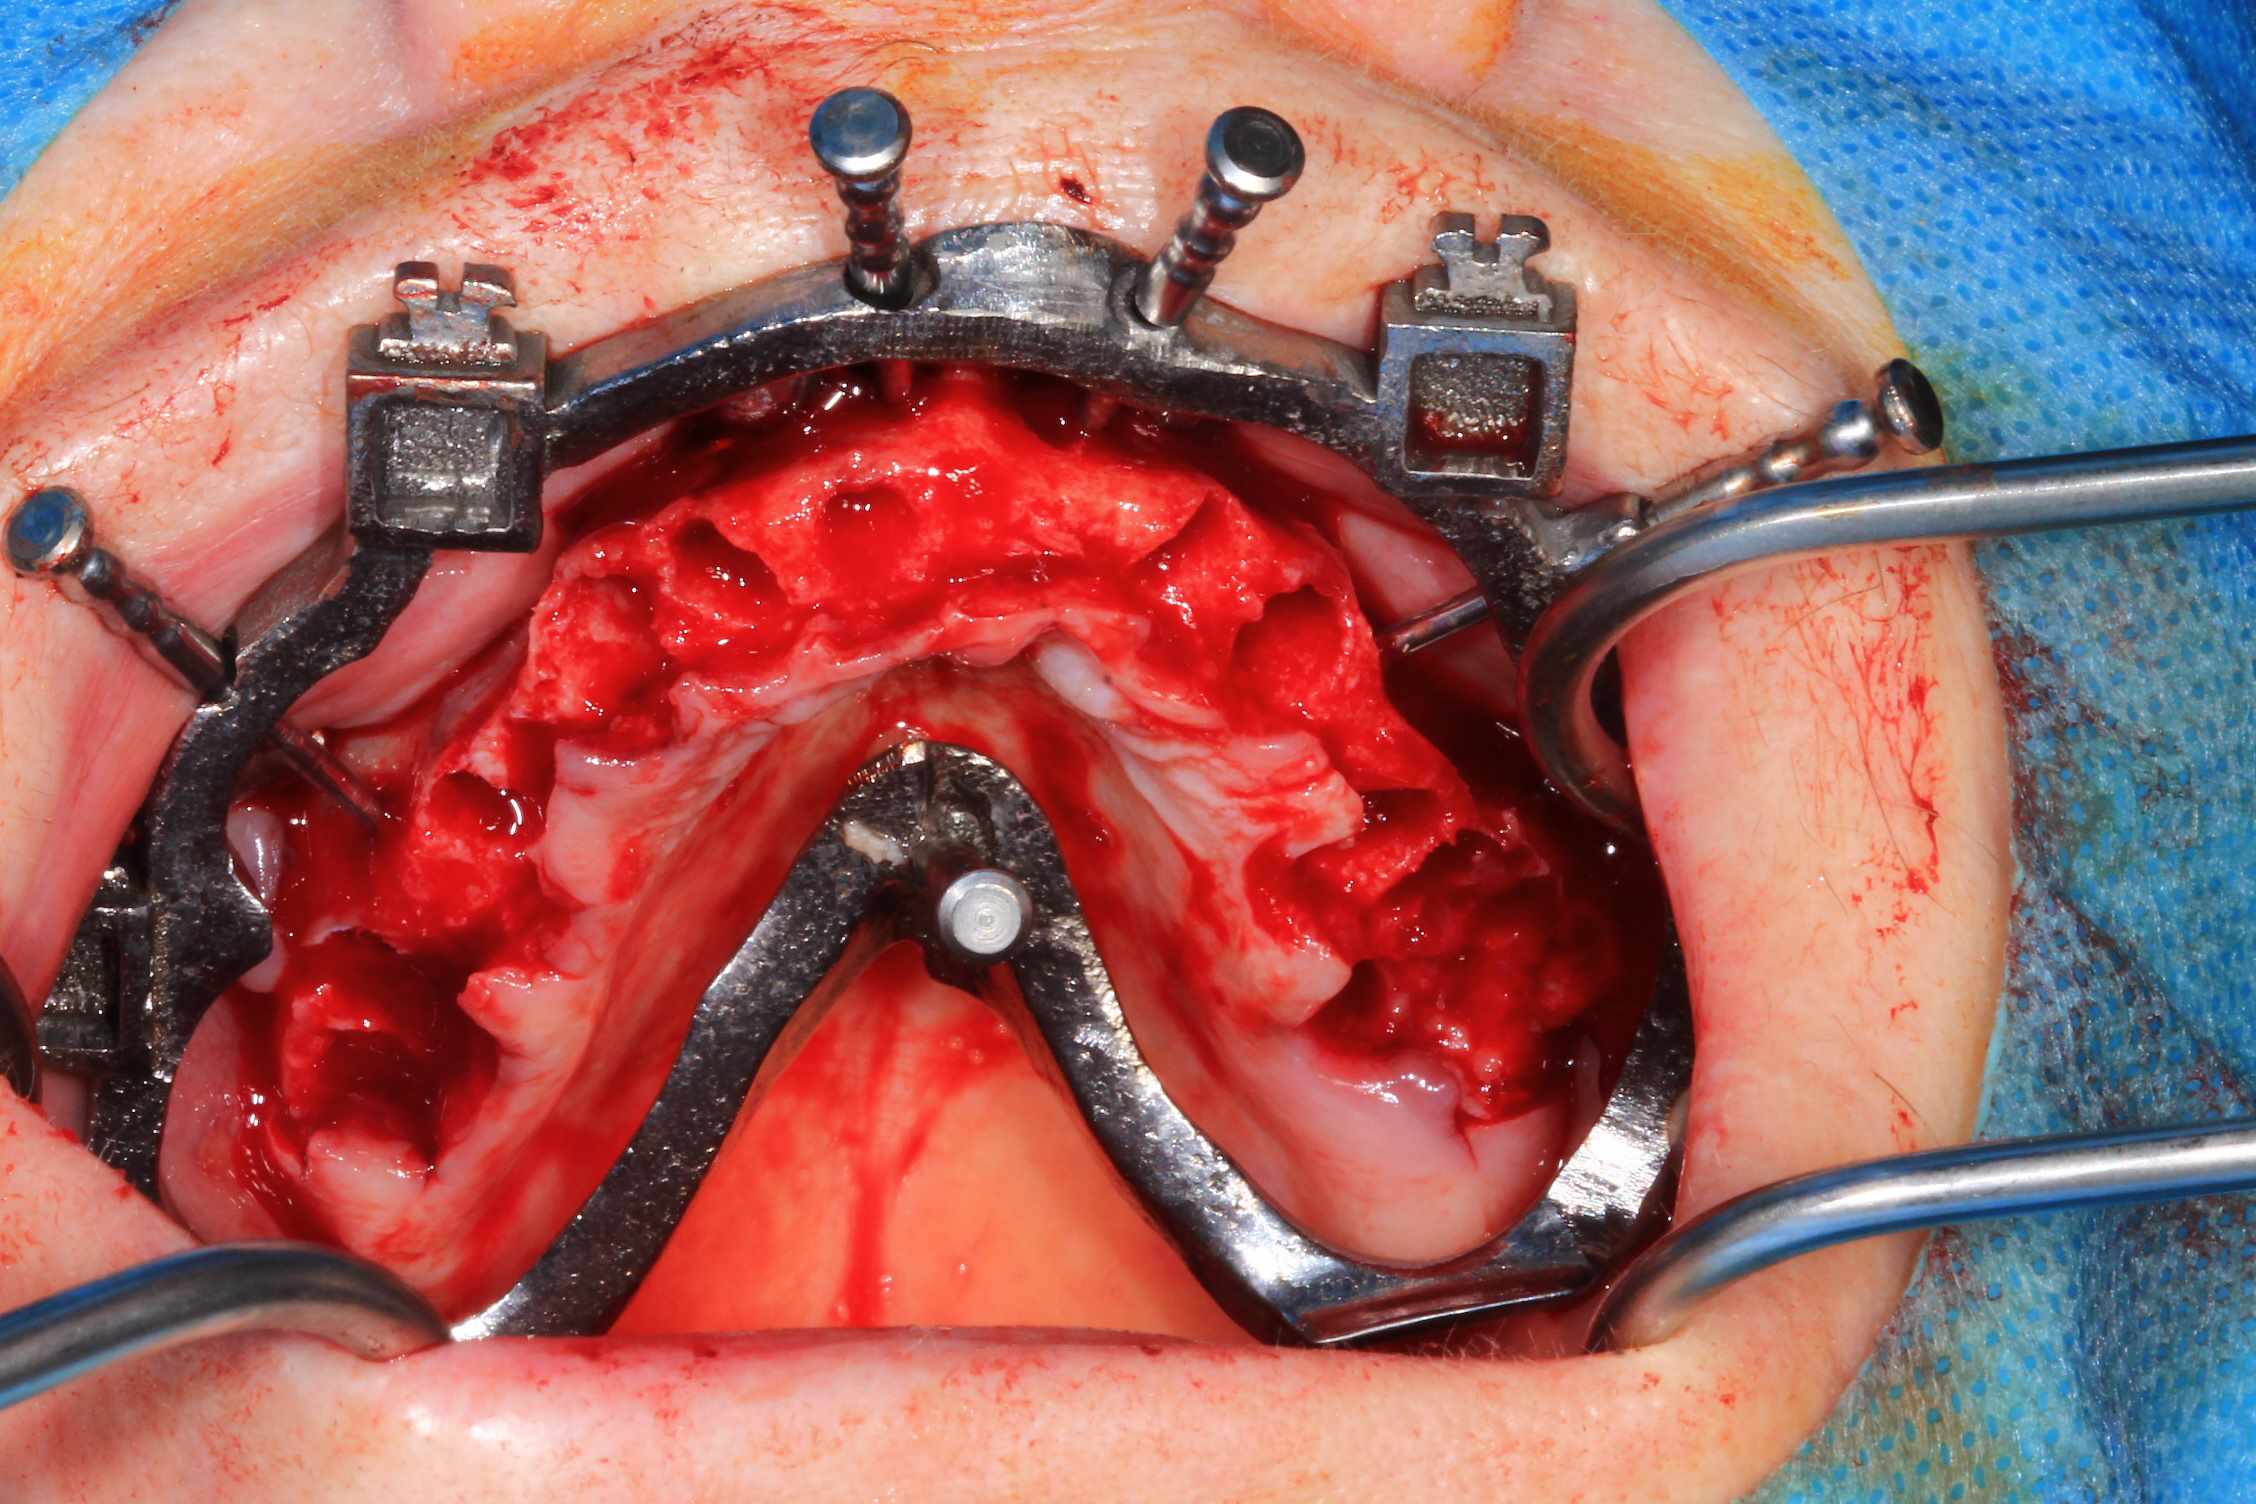

Cas 5 : extraction et all on 4. en bas , pas du tout d'os : décision de bridge complet avec une extension de chaque coté.

Modélisation : labo lio. Design et impression du guide : Teeth projet. Bridge full zircone katana myio rosenscrew en mise en charge instantanée , labo LIO.

Guide a etage avec fixtion de l'etage clavette par rapport aux dents avant extraction. Extraction.

Fixation du guide de forage sur le guide clavette. pose des implants, des piliers ( tres classique ), et du bridge zircone rosenscrew. Stickybone The Graft, sutures suspendues et résultat post op et un mois.